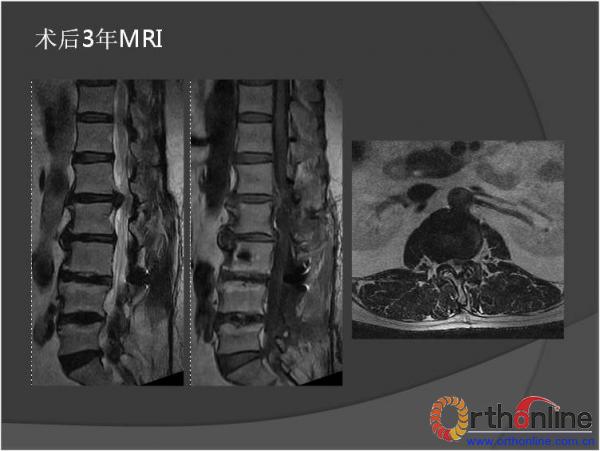

北京军区总医院骨科李放教授报告了一例腰椎管狭窄脊柱融合术后、退变侧凸加重并出现邻近节段退变病、而后进行翻修的病例。患者男性,64岁,2009年因腰椎管狭窄症行椎板减压,L3-4、L4-5PLIF手术,术后3年间疗效满意,后由轻度扭伤后再度出现腰痛及下肢疼痛,经检查后发现L2-3间盘退变、L1-2间盘突出并出现退变性腰椎侧凸,于2013年2月行翻修手术后痊愈。